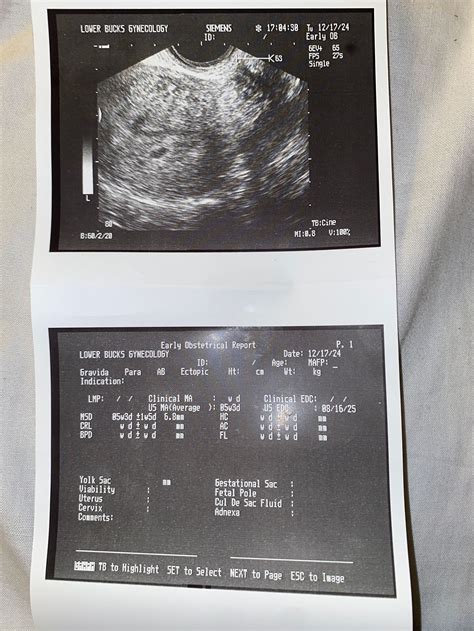

In the earliest weeks of pregnancy, your ultrasound technician is looking for specific markers to confirm that the pregnancy is progressing as expected. A fetal pole is essentially the first visible sign of the developing embryo. It appears as a thick, linear area of echoes on the ultrasound screen, usually situated alongside the yolk sac. While it might not look like a recognizable "baby" in the traditional sense, this structure is the foundation of the embryo, representing the longitudinal axis of the developing human body.

The fetal pole typically becomes visible via a transvaginal ultrasound around the 6th or 7th week of gestation. Because the embryo is incredibly small during this phase, the fetal pole often appears as a tiny, dense white line or a small, pill-shaped thickening. It is one of the most important milestones in early pregnancy because its presence confirms that an embryo has successfully implanted and begun the process of cellular differentiation.

Doctors use the measurement of the fetal pole, often referred to as the Crown-Rump Length (CRL), to estimate the gestational age of the pregnancy more accurately than using the date of your last menstrual period. Because embryos grow at a very consistent rate during the first trimester, this measurement allows your healthcare provider to confirm your due date with high precision.

When asking what is a fetal pole, it is also important to understand why clinicians take such precise measurements. The CRL—the measurement from the top of the head to the bottom of the torso—is a standard diagnostic tool. If the fetal pole measures within the expected range for your estimated weeks, it suggests a healthy pregnancy. If the measurements are significantly smaller than expected, it may lead to further monitoring or a follow-up scan to check for growth.